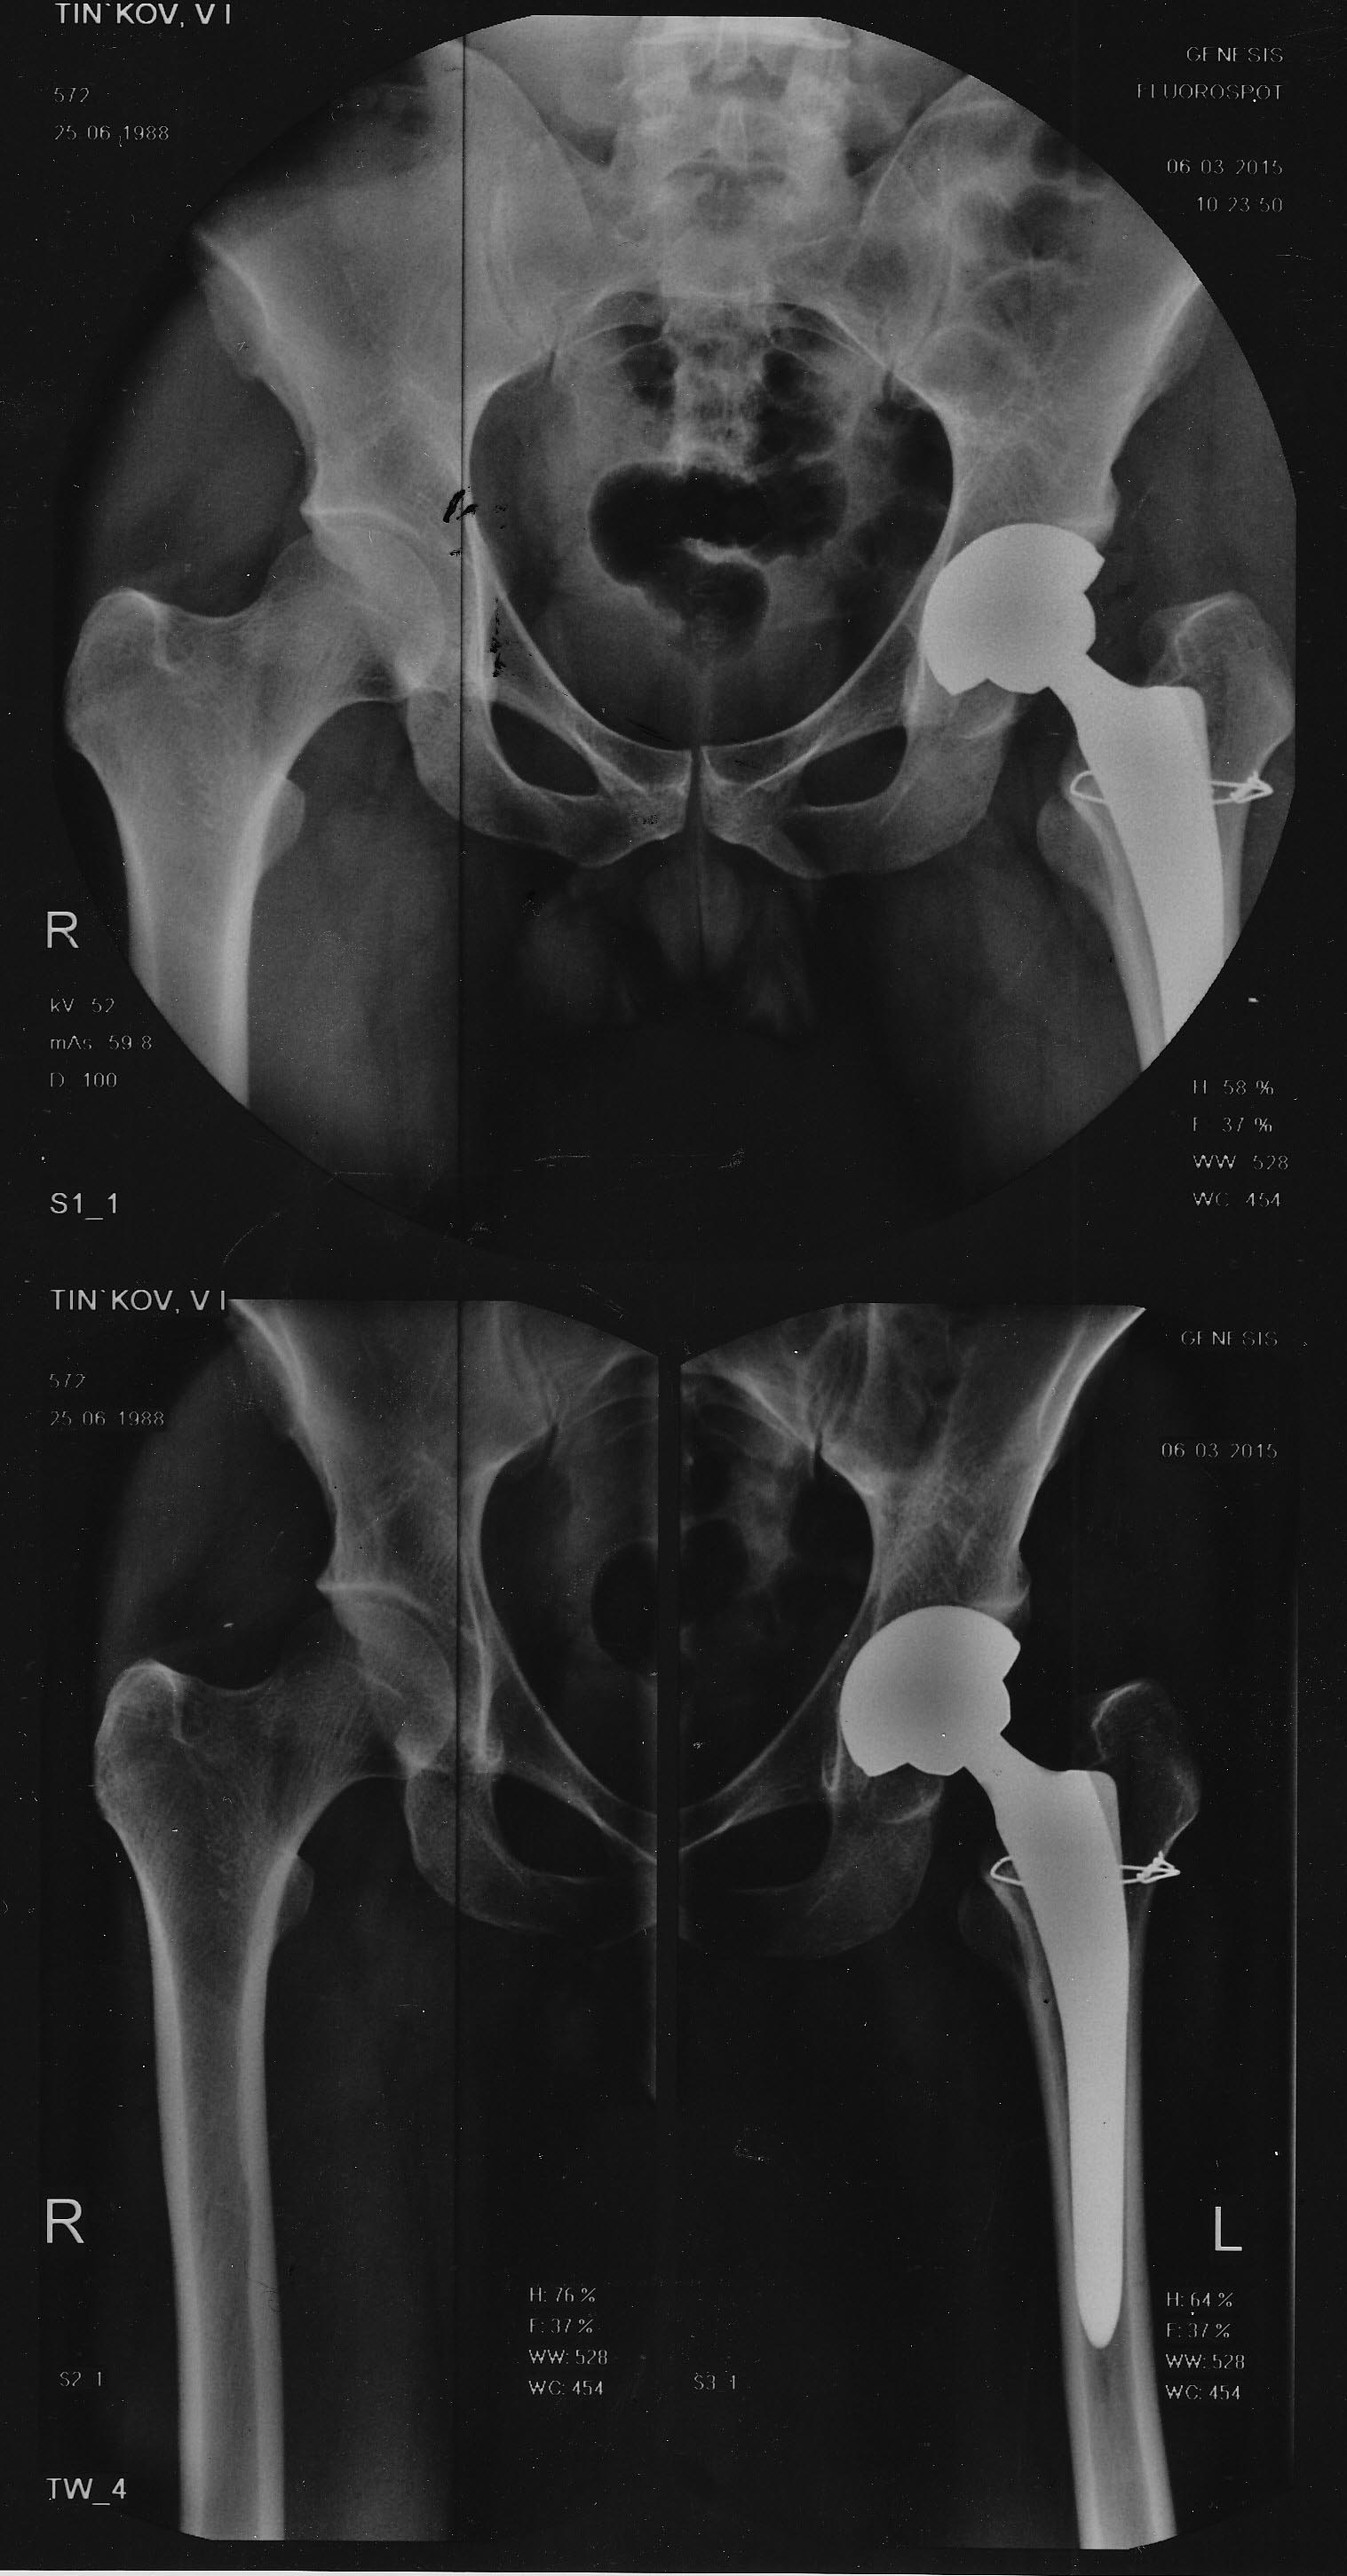

здравствуйте, выкладываю рентгенограммы, прошу прощения за отсутствие предоперационных снимков. выложить смогу только во вторник.

Иван, доброго Вам дня. Несколько сложновато сказать без предоперационных снимков, но складывается впечатление что ножка протеза не совсем оптимальна для данного канала по форме и размеру. Нельзя одним типом протеза прооперировать всех больных, ну может быть исключением являются цементные ножки, да и то не всегда. При малейшем несоответствии даже небольшие усилия клина достаточны для перелома, а как Вы знаете, ножка всегда больше рашпиля, поэтому если есть концентрация напряжения не по всей зоне контакта а на ограниченном участке - быть перелому. Это я хорошо знаю по ножке Споторно, ее нужно практически поставить руками и слегка пристукнуть. С другой стороны, эти переломы ведут себя очень благоприятно и через 3 месяца нет никаких проблем с ними. Как то так, с уважением, Р.Тихилов

Здравствуйте Коллега. На мой взгляд перелом был получен на этапе обработки рашпилем. Вы совершенно четко описываете мануальные ощущения перипротезного перелома, когда нет ощущения заклинивания ножки и она как-бы проваливается.Если ножка не заклинила на уровне последнего рашпиля и "пошла" дальше это 99% перипротезный перелом. На снимка ножка находится в вальгусном положение. Ножка Excia при риммирование канала имеет отличие от ножек типа Мюллера, Споторно тем, что ее не надо латеролизовать, прижимая к большому вертелу. Обработку необходимо проводить параллельно дуге Адамса, в соответствие с ее кривизной.В начале работы с ней целесообразно использовать контроль (ЭОП например)хотя бы 1-2 раза чтобы понять ее особенности. Второй важный момент планирование на правильно масштабных рентгенограммах. Если Вы запланировали ножку, а заклинивание рашпиля идет на меньших размерах, то это или не правильное планирование или неправильное положение рашпиля. Если есть возможность сделать КТ у данного пациента(настоятельно советую), то увидите, что конец ножки (рашпиля) упирается во внутренний кортикал где имеется перелом. Еще одна причина, когда ножка идет в заднем направление. Может быть сочетание кзади и кнаружи(кнутри). Думаю, что при Вашем опыте работы, сделав интаоперационные снимки на рашпиле, Вы все поймете с первого раза. Пациенту рекомендую наложить кокситную гипсовую повязку на срок не менее 3 месяцев. Ходьба без нагрузки!!! С уважением И.М. Пивень

предоперационный снимок